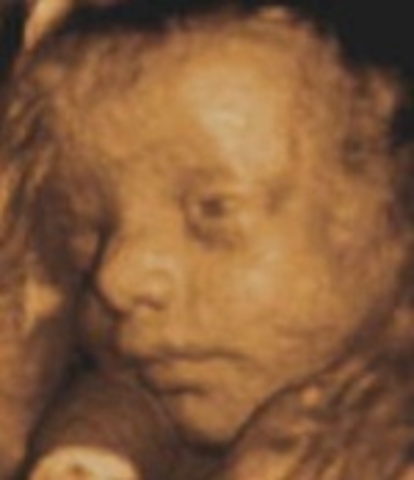

• Week 19: Genitals Recognizable

Week 19: Genitals Recognizable

Fetus is around 6.5 inches and 9 ounces, placenta continues to grow and nourish the baby, baby's heart can be visible during ultrasound, baby's genitlas are distinct and recognizable, scalp hair has sprouted and continues to grow